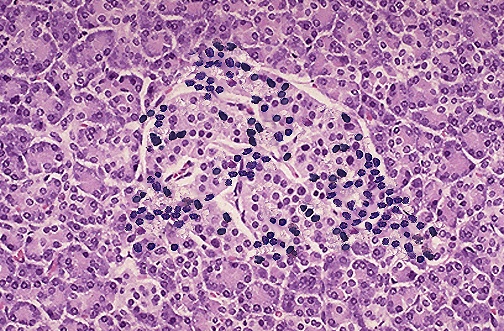

| This is an insulitis of an islet of Langerhans in a patient who will eventually develop type I diabetes mellitus. The presence of the lymphocytic infiltrates in this edematous islet suggests an autoimmune mechanism for this process. The destruction of the islets leads to an absolute lack of insulin that characterizes type I diabetes mellitus. |